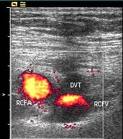

Biological agent use and operative time were risk factors in the development of acute surgical site infection and deep vein thrombosis after total knee arthroplasty, according to a study presented at the 2011 Annual Meeting of the American Academy of Orthopaedic Surgeons.

There were also 120 DVT-positive cases (30.6%) in the cohort, with analysis showing operative time, biological agent use, age and presence of diabetes mellitus to be risk factors.

“The use of biological agents was a risk factor for acute SSI and DVT after TKA,” Kawakami said. “Higher age and the presence of diabetes mellitus was a risk factor for DVT after TKA.”